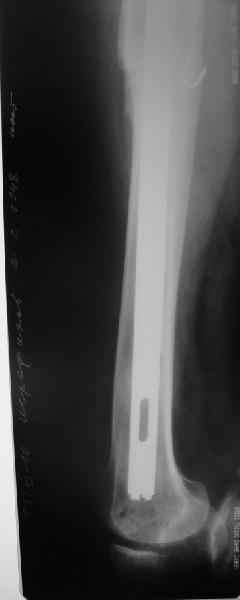

Дорогой Александр Николаевич! Спасибо, что держите всех нас в курсе.

Сейчас опорную нагрузку на бедро берет на себя система от бедренного компонента эндопротеза до проксимального винта в интрамедуллярном гвозде. Свидетельство тому - реакция кортикала утолщением вокруг того самого винта. Таким образом вся кость от верхушки б.вертела до проксимального винта не испытывает физиологической осевой нагрузки. Результатом этого могут стать следующие последствия друг друга не исключающие: 1) все будет хорошо до перелома опорной системы по винту(ам) или в месте соединения штифта с ножкой или еще где-либо, 2) исключенная из-под нагрузки кость будет терять в количестве и качестве, что не очень (или очень не) хорошо для возможных будущих ревизий (тьфу-тьфу!!!).

Хотел бы обратить Ваше внимание, что реакция кортикала наблюдается только вокруг проксимального винта, дистальный винт не испытывает подобной нагрузки. Отсюда еще одна умозрительная авантюра - выкрутить только проксимальный винт. Изменения кости вокруг дистального винта тоже могут дать ответ на счет интеграции ножки, также как и появляется возможность сломать его. Страховаться (затратнее, но надежнее) или нет(легче, но не безопасно) динамическим винтом - на Ваш выбор.

О качестве сращения перелома тоже сказать трудно. Выраженной мозоли нет. В боковой проекции отломки накладываются друг на друга. В прямой проекции зона перелома в наружной части закрылась не полностью. Возможно причина тому - недогрузка кости.